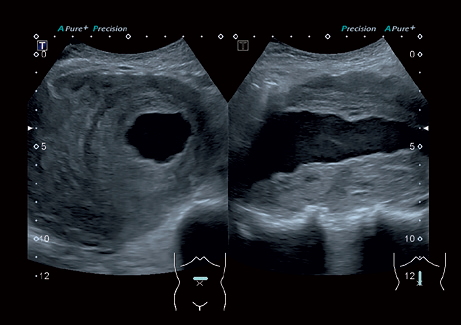

Система Aplio 300 – идеальный вариант для тех, кому нужна надежная и эффективная работа оборудования в ежедневной практике. Эта высокопроизводительная, универсальная и экономичная система предлагает получение качественных изображений с впечатляющей глубиной и детализацией в самых разных областях медицины.

• Превосходное качество визуализации и детализации анатомических структур для широкого спектра областей использования.

• ApliPure - технология повышения качества изображения

• Precision Imaging - технология получения изображений мелких деталей с четко очерченными границами и высокой однородностью